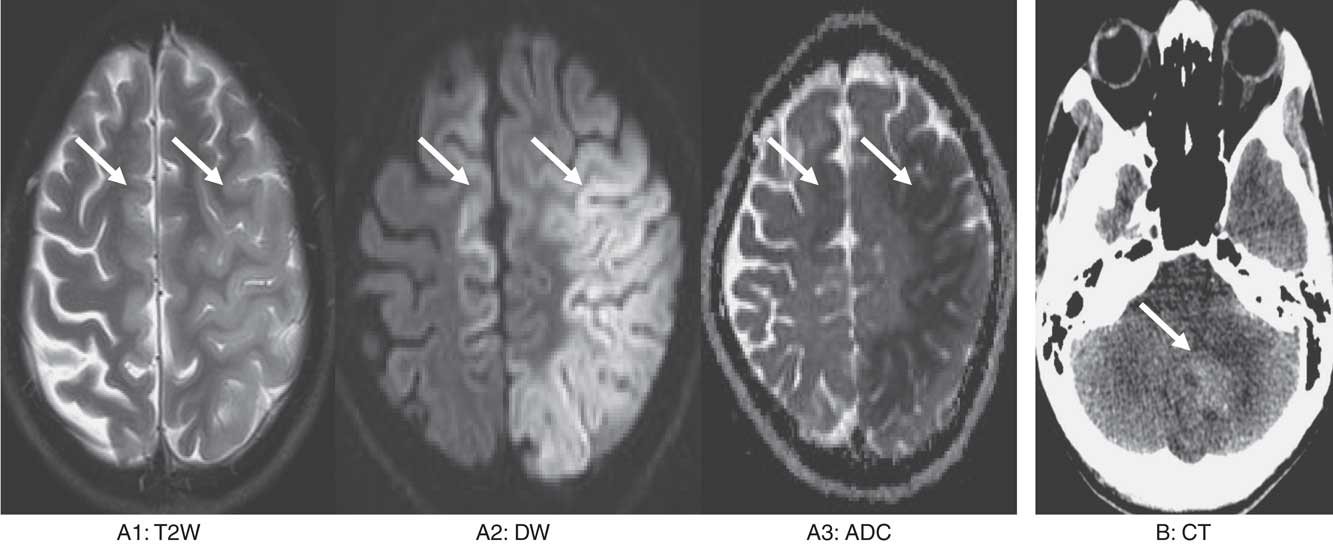

A total of 32 patients with scorpion sting and 35 patients with snake envenomation were included in the review, as shown in Table 1. Mean ages of patients with snake and scorpion envenomation were 43 and 33 years, respectively. There was a male preponderance among both the groups. Clinical features of depressed sensorium and hemiparesis were present in more than one-third of the patients with snake envenomation. Hemiparesis was present in more than half of the patients, and depressed sensorium was present in one-third of the patients with scorpion envenomation. CT brain was the most common neuroimaging performed for 54% and 81% of patients with snake and scorpion envenomation, respectively. Infarcts were the most common patterns of CVI and were seen in 88% and 53% with snake and scorpion envenomation, respectively. Among these, 68% of patients with snake envenomation and 47% of patients with scorpion sting had multiple infarcts. More than one infarct was defined as multiple infarcts. In all, 48.5% of patients with snake envenomation and 28.5% of patients with scorpion sting had infarcts bilaterally. Among the controls, 26 (74%) had infarcts, seven (20%) had hemorrhages and two (6%) had hemorrhagic infarcts. Among the controls, 13 (50%) infarcts were multiple and six (23%) were bilateral. Hemorrhages were more among patients with scorpion sting (41% vs. 6%). In all, 92% of patients with hemorrhage had single and unilateral involvement. Among the controls, all bleeds were single and unilateral. In the patients with scorpion sting, the most common sites of hemorrhage were capsuloganglionic region, similar to the controls, as shown in Table 2. The most common sites of infarcts following both the envenomations were parieto-occipital, cerebellar and capsuloganglionic and frontal region, respectively (Images 1 and 2). These were also similar to the topography of infarcts in age-matched controls (Table 2). Mortality in patients with cerebrovascular accidents following snake envenomation was 8%, as compared with 28% in patients with scorpion envenomation and 5.7% in age-matched controls.

Image 1 Image series (A) a 36-year-old man with snake bite. T2 weighted (T2W) shows swelling and hyperintensity in left middle cerebral artery and right anterior cerebral artery territory with associated diffusion restriction suggestive of acute infarct. (B) A 38-year-old man with snake bite. Non-contrast CT shows acute hematoma in the left cerebellar hemisphere with surrounding edema.

Both CT and MRI have been used for confirmation of CVI among these patients. CT brain was performed for 75% of patients with scorpion sting and 53% of patients with snake envenomation in our review. Although CT is adequate to establish the diagnosis, an MRI with diffusion restriction is ideal in differentiating dilated venules and artifacts, which could be mistaken for infarcts.Reference Mishra, Arvind and Muliyil 30 In both, infarcts and hemorrhages can be seen, with the former being common. Infarcts tend to be bilateral and multiple. Infarcts following both the envenomations were predominant in parieto-occipital, cerebellar and capsuloganglionic regions, respectively (Images 1 and 2). Involvement of bilateral anterior cerebral artery, middle cerebral artery and the posterior cerebral artery is common, with the involvement of bilateral posterior cerebral artery reported to be most common.Reference Kumar, Babu and Agrawal 31 – Reference Thacker, Lal and Misra 39 The uncommon neurological involvements that have been reported are the presence of thalamic infarct, lateral medullary syndrome and brainstem infarcts.Reference Ittyachen and Jose 24 , Reference Kumar, Babu and Agrawal 31 , Reference Fernández-Bouzas, Morales-Reséndiz, Llamas-Ibarra, Martínez-López and Ballesteros-Maresma 35 , Reference Thomas, George, Mishra, Mannam and Ramya 40 Hemorrhages tend to be unilateral and single. Common sites of hemorrhage are capsuloganglionic region, cortical and cerebellar, respectively (Table 2) (Images 1 and 2). Patients can also present with coexistent infarcts and hemorrhages, which was 6% in this review.Reference Namal Rathnayaka, Kularatne, Kumarasinghe, Ranaweera and Nishanthi Ranathunga 11 , Reference Boviatsis, Kouyialis, Papatheodorou, Gavra, Korfias and Sakas 32